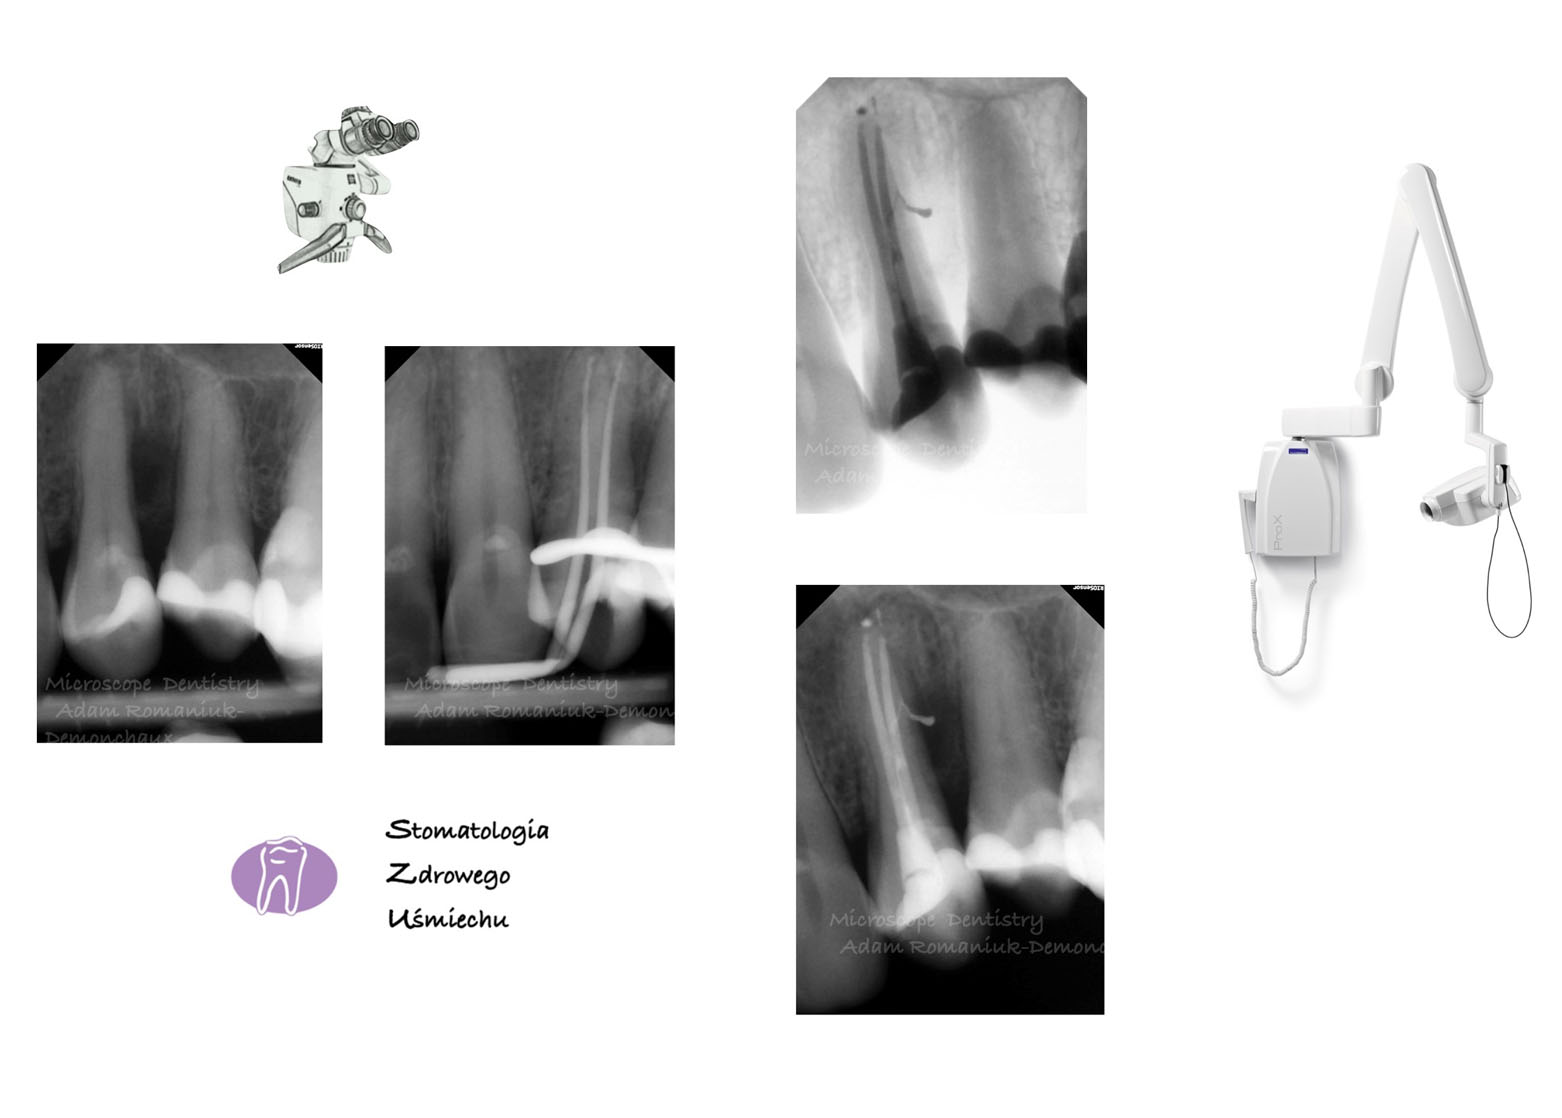

Endodoncja mikroskopowa

W Naszym Gabinecie stosowane są najwyższe standardy, dlatego również leczenie kanałowe odbywa się pod mikroskopem zabiegowym. Precyzja, możliwość obserwacji szczegółów anatomicznych i wykonywanych procedur podczas pracy w powiększeniu i dobrym oświetleniu jakie zapewnia mikroskop stomatologiczny, umożliwia uzyskanie wysokiej skuteczności prowadzonego leczenia. Kanały opracowywane są maszynowo oraz dokładnie oczyszczane chemicznie z zastosowaniem ultradźwięków i wypełniane termicznie. Jest to nowoczesne podejście kliniczne. Mikroskop używany podczas leczenia endodontycznego zwiększa skuteczność prowadzonej terapii i bardzo często pozwala po wykonaniu właściwej rekonstrukcji uniknąć utraty zęba.